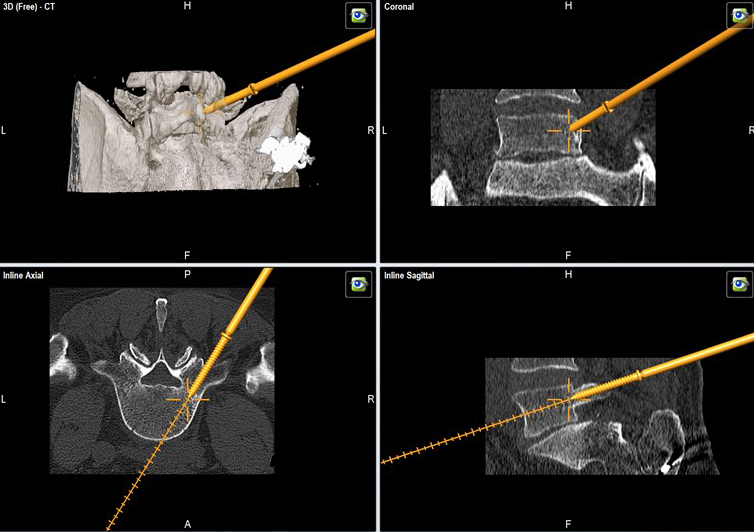

A 52-year-old male patient presented with low back pain and S1 radicular pain on the left side for 3 weeks. The laboratory tests of the blood showed enhanced inflammation signs. The MRI showed an infection of the L5/S1 disc (Fig 1). Indications for minimally invasive spondylodesis with intervertebral cage (Figs 2-6).